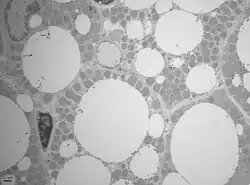

El tejido adiposo o tejido graso es el tejido de origen mesenquimal (un tipo de tejido conjuntivo) conformado por la asociación de células que acumulan lípidos en su citoplasma: los adipocitos.

Existen dos tipos de tejido adiposo, el tejido adiposo blanco (o unilocular) y la grasa parda (o multilocular).

El citosol y el núcleo quedan reducidos a una pequeña área cerca de la membrana. El resto es ocupado por una gran gota de grasa. El tejido adiposo, que carece de sustancia fundamental, se halla dividido por finas trabéculas de tejido fascicular en lóbulos.